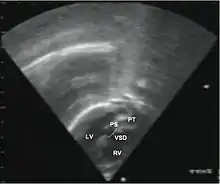

قد يكشف مقدم الرعاية الصحية عن لغط قلبي أثناء الاستماع إلى الصدر بالسماعة الطبية، ويكون لون جلد الطفل وفمه أزرقًا. وغالباً ما تشمل الاختبارات ما يلي:

- الأشعة السينية على الصدر، الأشعة السينية على الصدر، تحول الأوعية الكبرى يظهر عادة صورة ظلية للقلب المنصف على أنها "بيضة على سلسلة"، حيث القلب المتوسع يمثل بيضة على الجانب والغدة الصعترية الضامرة من المنصف العلوي تمثل السلسلة.

- مخطط صدى القلب (إذا تم ذلك قبل الولادة، يُسمى مخطط صدى القلب الجنيني)